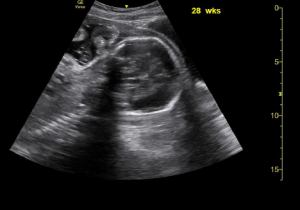

Sagittal and transverse